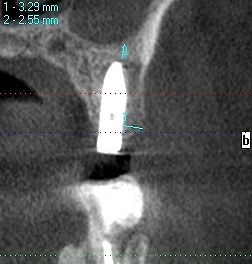

口蓋側寄りに埋入しています

頬側は骨造成をしています頬側は

頬側は骨が3mm以上ないといけません